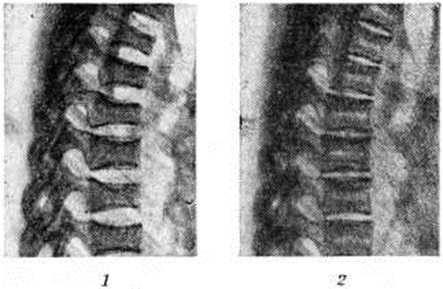

Остеопороз имеет обычно однородный мелкозернистый характер, отличаясь этим от крупнопятнистых деструктивных очагов при воспалительных или бластоматозных процессах. Наблюдается остеопороз чаще в средних, нижних грудных и верхних поясничных позвонках, реже в верхних грудных и ещё реже в шейных позвонках. Тела позвонков уплощаются, деформируются по типу «рыбьих» (рис. 2, 1). Остеопороз рёбер и грудины проявляется небольшой интенсивностью теней костей и груботрабекулярной их структурой; места переломов бывают окружены быстро возникающими избыточными мозолями. Столь же часто остеопорозу подвергаются кости таза, кистей и стоп. Рост и дифференцировка скелета у детей отстают в среднем на 3 года.

Рис. 2.

Рентгенограммы (боковые) грудного отдела позвоночника при болезни Иценко— Кушинга: 1— выражено уплощение тел позвонков («рыбьи позвонки»); 2— то же наблюдение после успешного лучевого лечения (высота тел позвонков увеличилась, виден двойной их контур).

Процесс восстановления структуры костей является одним из основных критериев эффективности лечения Иценко – Кушинга болезнь; у детей наряду с восстановительным процессом в костной ткани отмечается и ускоренное появление ядер окостенения. При этом значительно увеличивается высота тел отдельных позвонков, уменьшается ширина межпозвонковых дисков; тела позвонков приобретают двойные контуры (рис. 2, 2).